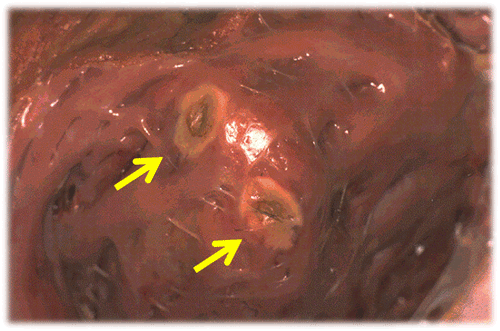

Hình 2: Tổn thương mô tim gây ra bởi năng lượng tần số radio là các vùng nội mạc bị biến mầu do nhiệt độ (mũi tên)